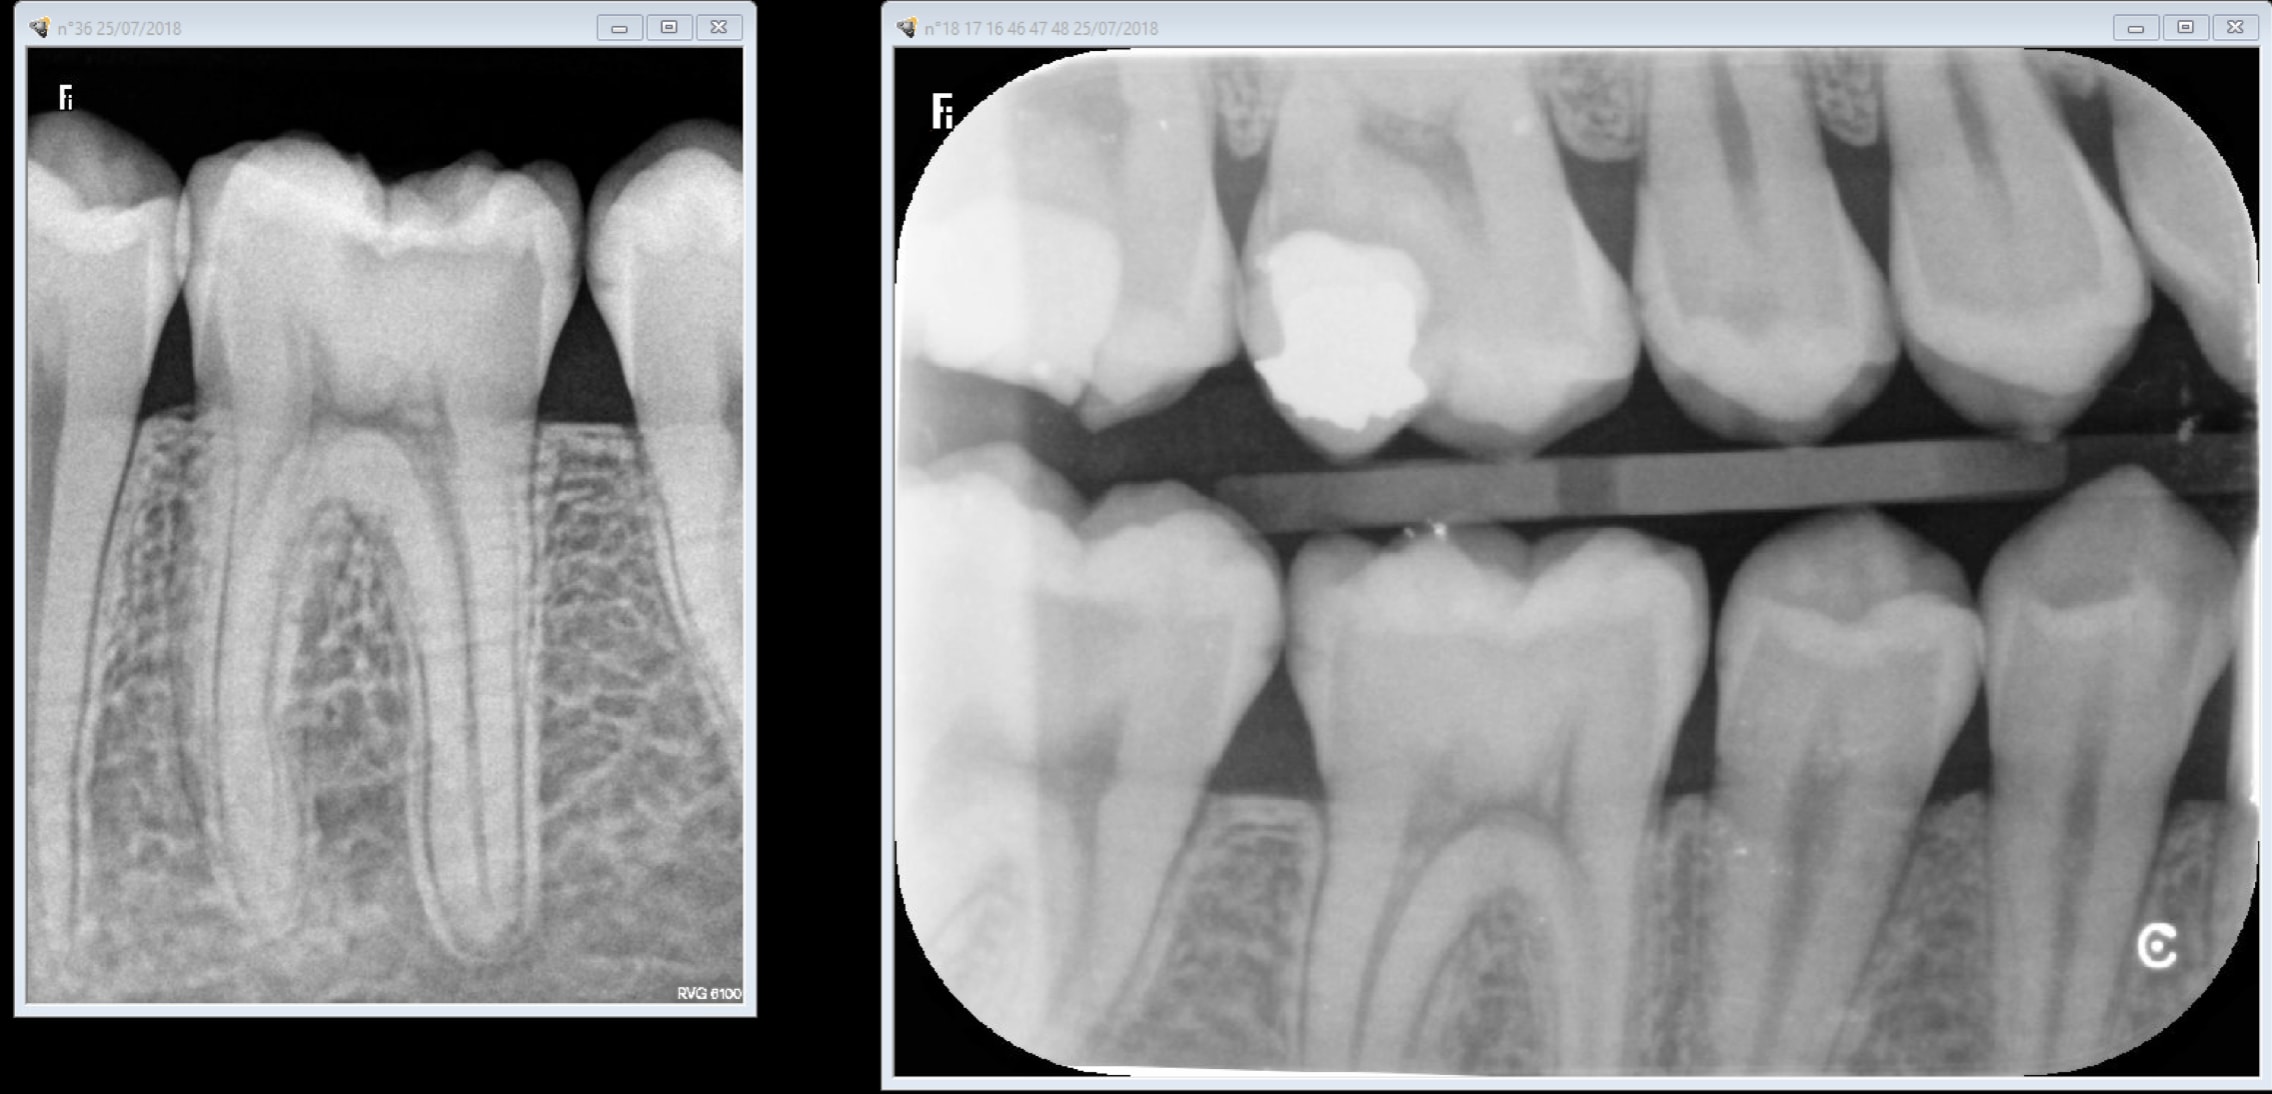

OK une autre plaque faut jouer avec les filtres avec le capteur non. Ca se ruine assez vite les plaques et ça vaut la peau du derche. Excuses moi le capteur est plus vieux de 5 ans que ces plaques de merde.

Capture d écran 2018 07 25 20.21 - Eugenol

C'est un constat plaques vieilles ou pas plus de boulot à tirer un cliché valable ( gestion du temps d'expo par ex, faire gaffe à ce qu'elles ne prennent pas la lumière au développement ensacheter dés-ensacheter). Le capteur c'est 0,09 s de temps d'exposition point barre. J'ai les 2 bordel pour moi il n'y a pas photo. Faut pas acheter des capteurs de merde non plus. Quand t'en fais 2 dans ta journée tu peux t'appliquer mais quand t'en fais 50 ca commence à etre casses burnes. -)))

Amusez vous bien avec vos plaques. -)))

Capture d écran 2018 07 27 00.23 - Eugenol